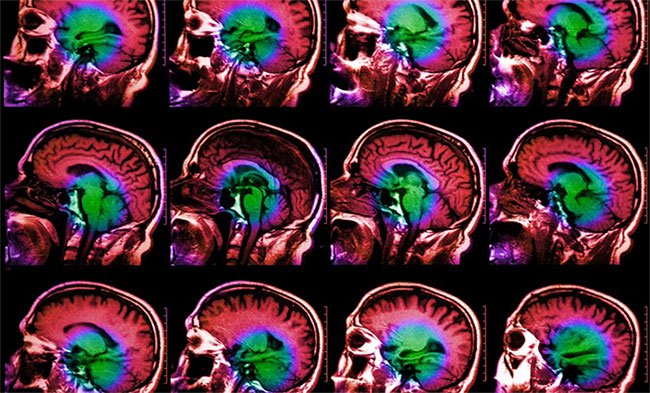

Nỗi buồn của bạn trông như thế nào trong não? Các nhà nghiên cứu đã sử dụng EEG để tìm ra câu trả lời cho vấn đề. Não sẽ tăng sự giao tiếp giữa amygdala (vùng não liên quan đến xử lý cảm xúc) và đồi hải mã (liên quan đến trí nhớ).

Một nghiên cứu được công bố trên Cell cho thấy các nhà khoa học đã lắng nghe các cuộc trò chuyện điện trong não - nói cách khác, các tín hiệu mà các vùng não gửi cho nhau. Khi một người cảm thấy suy sụp, các nhà nghiên cứu phát hiện sự giao tiếp tăng lên giữa các tế bào não ở hai vùng liên quan đến trí nhớ và cảm xúc.

Các nhà nghiên cứu sử dụng kỹ thuật điện não đồ nội sọ (EEG) để cấy các điện cực hoặc dây hộp sọ trong và trên não. Những điện cực được cấy ghép này ghi lại hoạt động của các tế bào não.

21 bệnh nhân tham gia thí nghiệm này trong khoảng 10 ngày. Kết quả cho thấy 13 trong số 21 bệnh nhân tâm trạng xấu có liên quan đến sự gia tăng giao tiếp giữa amygdala (vùng não liên quan đến xử lý cảm xúc) và đồi hải mã (liên quan đến trí nhớ).